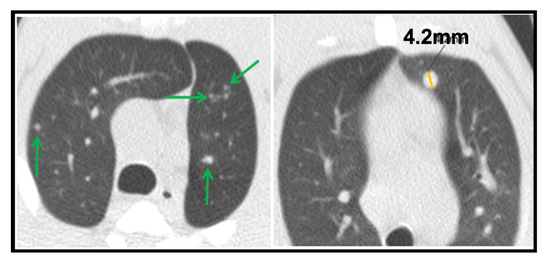

- Micronodule is a small solid lung nodule with smooth margins.